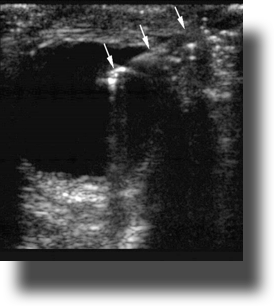

- Figure 10. Orbital cellulitis. Long arrow shows hypoechoic rim concerning for postseptal fluid tracking posterior to the globe. Short arrow shows thickening of the posterior segment of the eye.12 (Source: Seif D et al.13)

Retrobulbar Hematoma (RH) or Orbital Emphysema

- RH can be secondary to traumatic or nontraumatic causes.

- It will appear as a hypoechoic area posterior to the globe and may distort the posterior globe.

- Orbital emphysema is air tracking along the posterior surface of the globe, and it will cause “dirty shadowing,” which is shadowing that is bright white and obscures the structures in the far field.

- Figure 12. Triangular hypoechoic area (white arrow) suggestive of retrobulbar hematoma also known as “Guitar Pick Sign.”